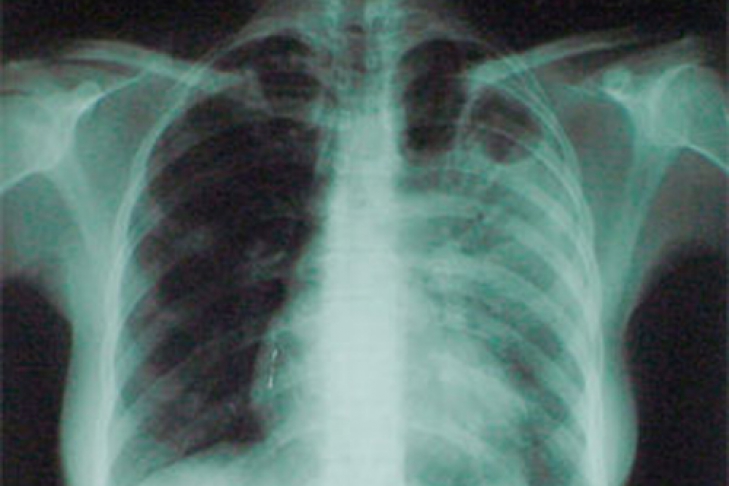

В Украине распространяется новая форма туберкулеза

Мутировавший вирус не проявляет никаких симптомов на ранней стадии заболевания

В Киеве состоялся брифинг на тему «Проблемы развития туберкулеза в Украине». На брифинге Глава правления Фундации «Общественное движение «Украинцы против туберкулеза» Виталий Руденко заявил, что в Украине прогрессирует новая разновидность туберкулеза, которая не проявляется никакими симптомами на ранних стадиях болезни.